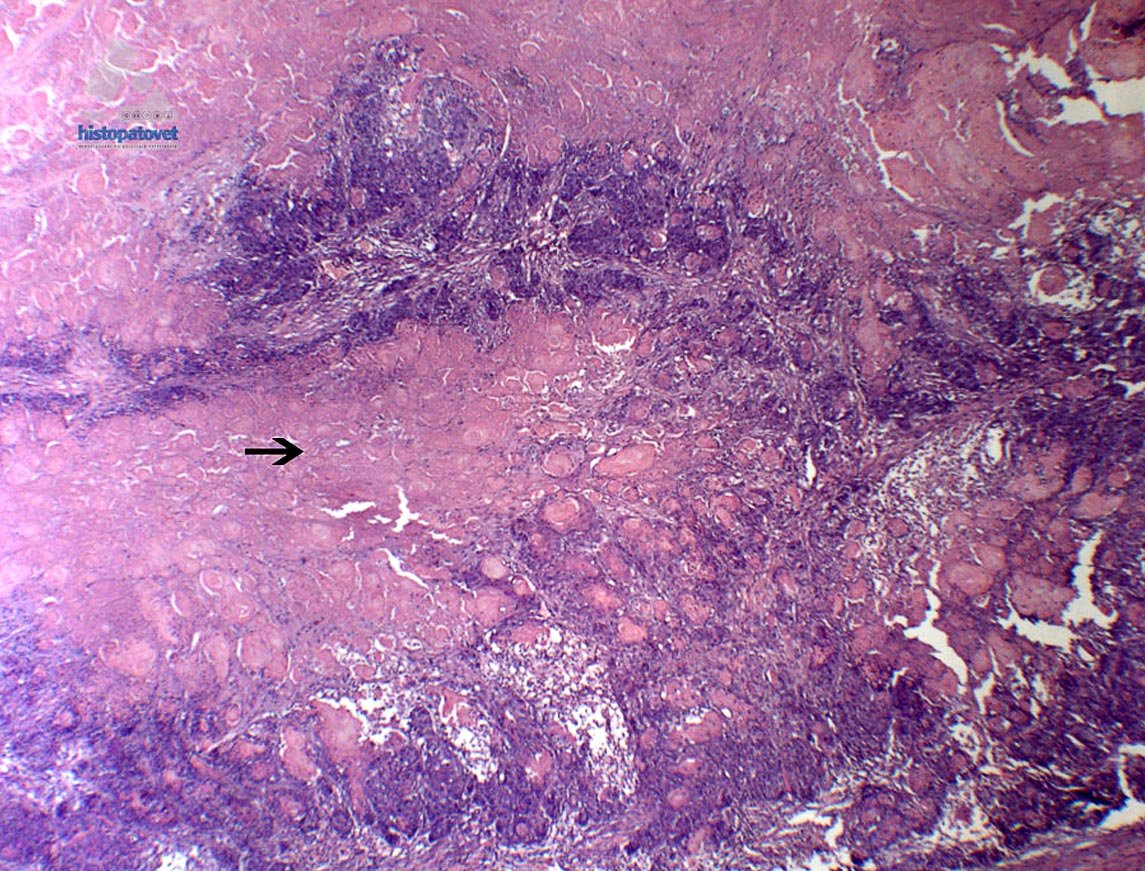

Hallazgos microscópicos: Masa parcialmente encapsulada, con mucha necrosis(Fig. 3).

Además, hay un crecimiento de células neoplásicas, con un patrón solido. Son células polimórficas, basofílicas (Fig.4).